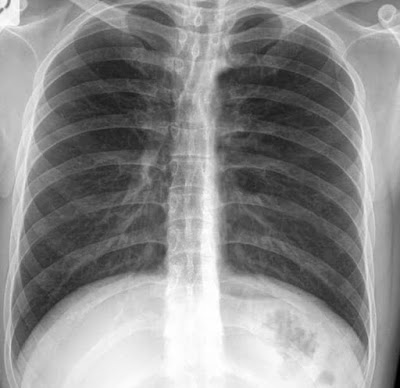

Hemoptysis causes

Image